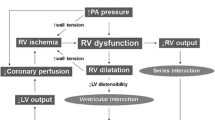

In hemodynamically unstable patients, it is important to optimize the fluid status of the patient, as volume contraction could contribute to hypotension and fluid overload and could worsen RV dysfunction. The ESC guidelines recommend a fluid challenge with 500 ml of normal saline over 15–20 min. Monitoring pulmonary pressure with a pulmonary artery catheter (Swan-Ganz catheter) is not recommended in PE patients. Alternatively, central venous pressure monitoring could provide a good indirect measure of the patient’s fluid status [72••].

In patients with massive PE, the use of inotropes and vasopressors are necessary to maintain adequate coronary perfusion and cardiac output. Low-dose epinephrine improve RV dysfunction due to inotropic properties [89]. Dobutamine improve arterial pressure, increases RV contractility, normalizes RV–pulmonary artery coupling and improves cardiac output [90]. Animal studies suggest benefits using milrinone and levosimendan in acute PE by improving RV contractility, decreasing pulmonary hypertension with lower risk of tachyarrhythmias [91, 92].